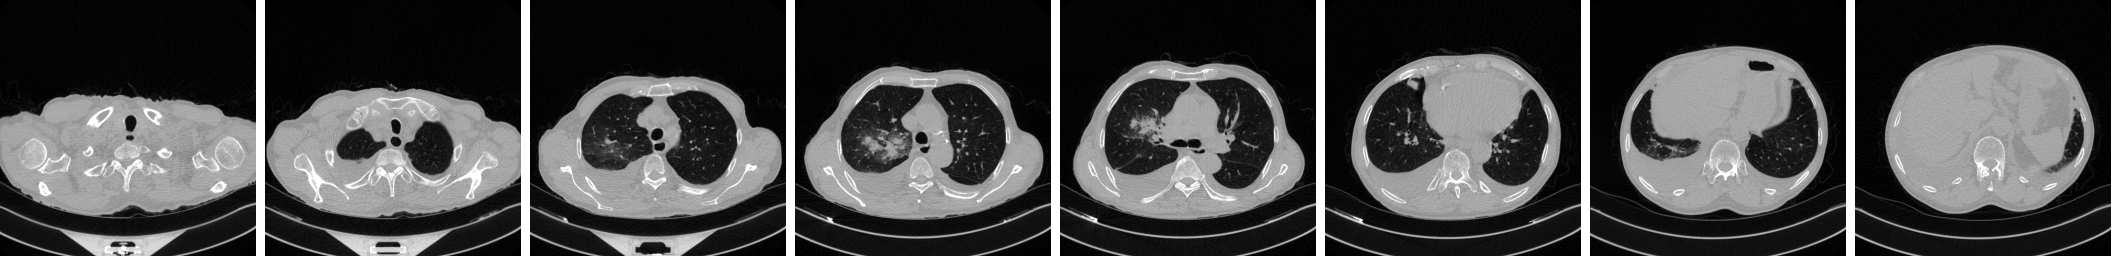

A new dataset (IST-C) is collected at Istanbul University-Cerrahpaşa, Cerrahpaşa Faculty of Medicine (IUC), consisting of 712 chest CT scans collected from 645 patients. It includes samples from COVID-19 infected patients, as well as normal lung parenchyma and Non-COVID-19 pneumonia, tumors and emphysema patients. Figure 1 shows three samples from the IST-C dataset collected in this work, including a typical COVID-19 involvement pattern termed as ground glass opacity, along with normal lung parenchyma and other conditions including non-COVID-19 pneumonia, tumors and emphysema.

Sample images extracted from COVID-19, ”Normal” and ”Other” classes are shown in Figure 1. The anonymized dataset is now shared publicly at http://github.com/suverim.

Lung shapes vary greatly within a chest CT scan, as can be seen in Figure 1. With the aim of focusing on the lung areas, we used the pretrained U-Net network to segment lung regions from non-lung areas.